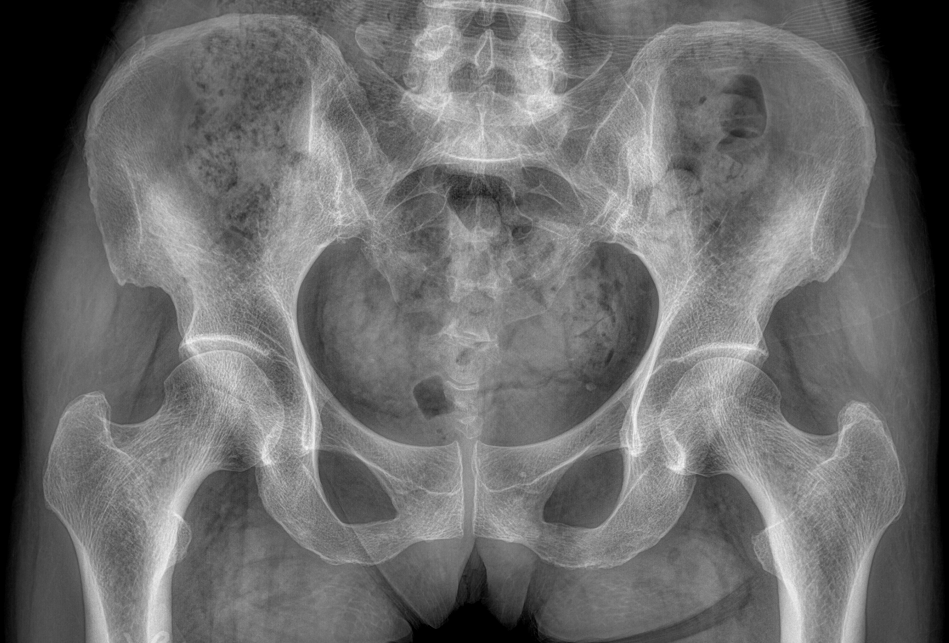

• 拍片

适用于全身各部位摄影

(常规摄影和特殊摄影)